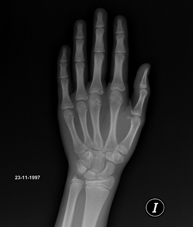

Procediment que usa els raigs X a través de la qual s'obtenen imatges de la pelvis per al seu estudi, especialment dels ossos pèlvics. - RX Edat òssia

Estudi que mitjançant una radiografia de la mà permet valorar, en funció del desenvolupament dels ossos, l'edat del pacient i determinar si existeix un retard o un creixement superior pel que correspon a la seva edat. - RX Malucs pediatria